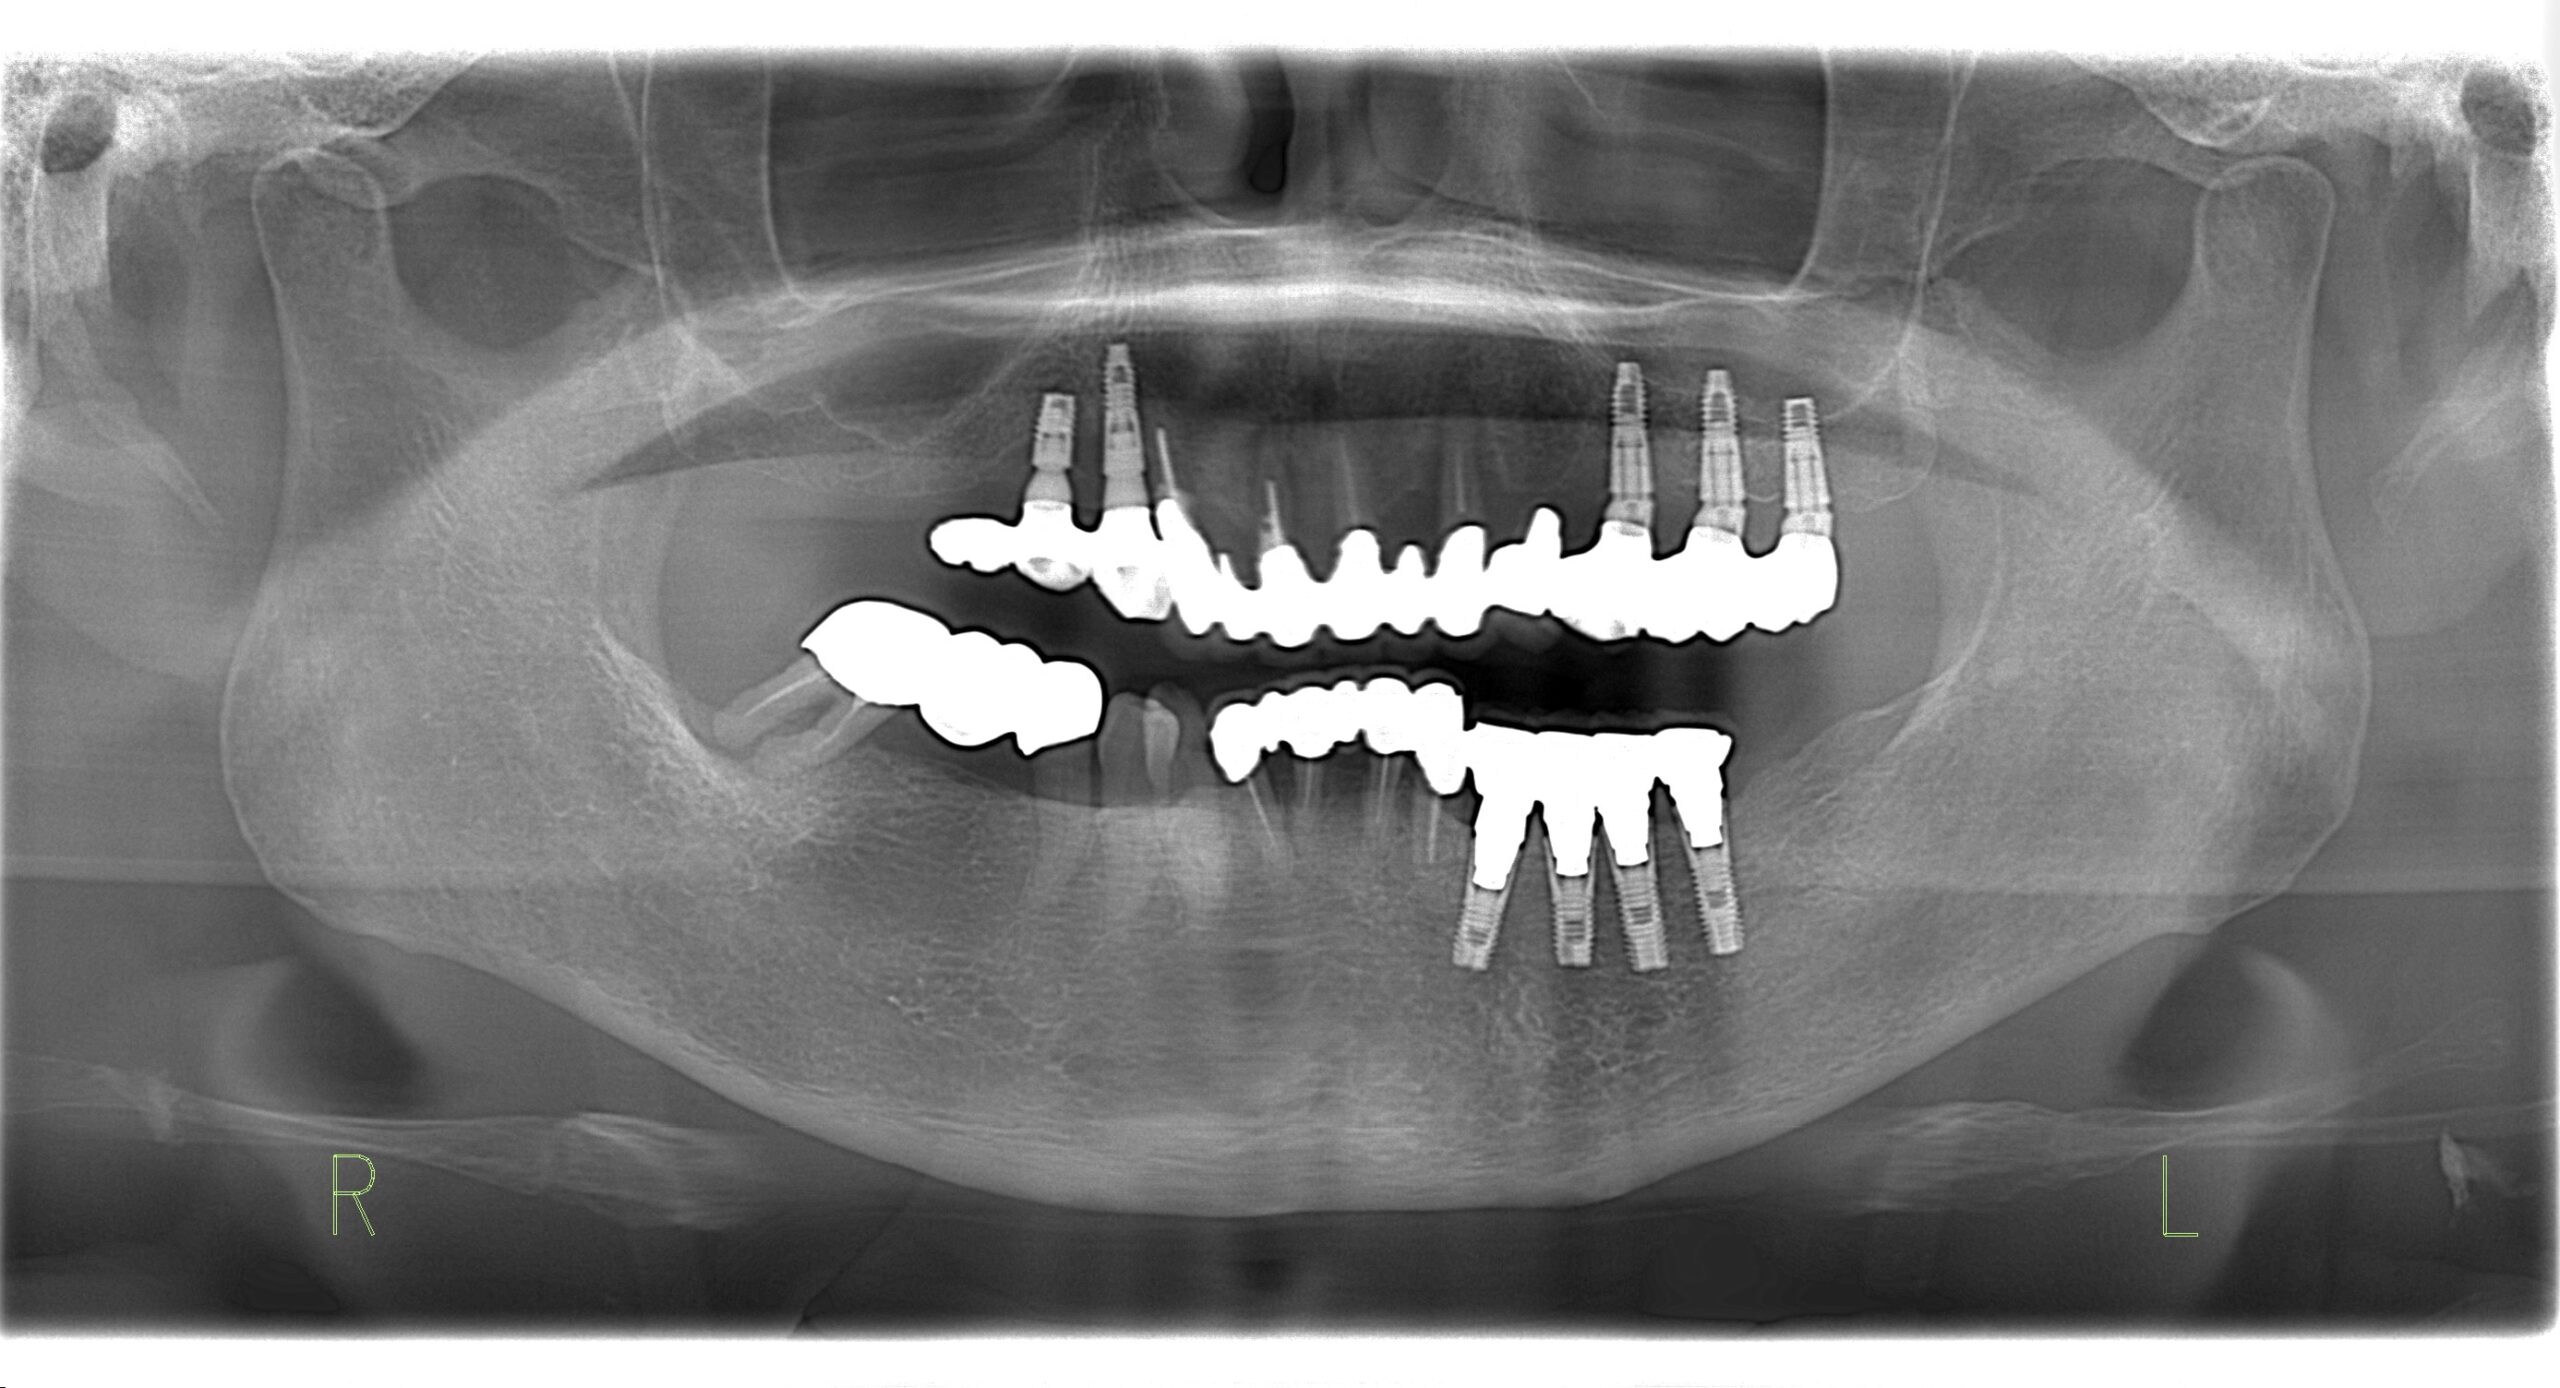

歯科用CT

従来のレントゲンは平面の撮影画像なので、骨の厚さや硬さを正確に診断することが難しいですが、CTは3次元による高画質画像なので、骨の厚さや幅、歯の根の状態まで正確に診断が可能です。

インプラント治療は手術前に口腔内状態をどれだけ正確に把握し、しっかりとした計画が立てられるかが重要です。

当院ではインプラント治療前にはCT撮影を行い、患者さまの口腔内の状態をしっかりと把握した上で治療を行っておりますのでご安心ください。